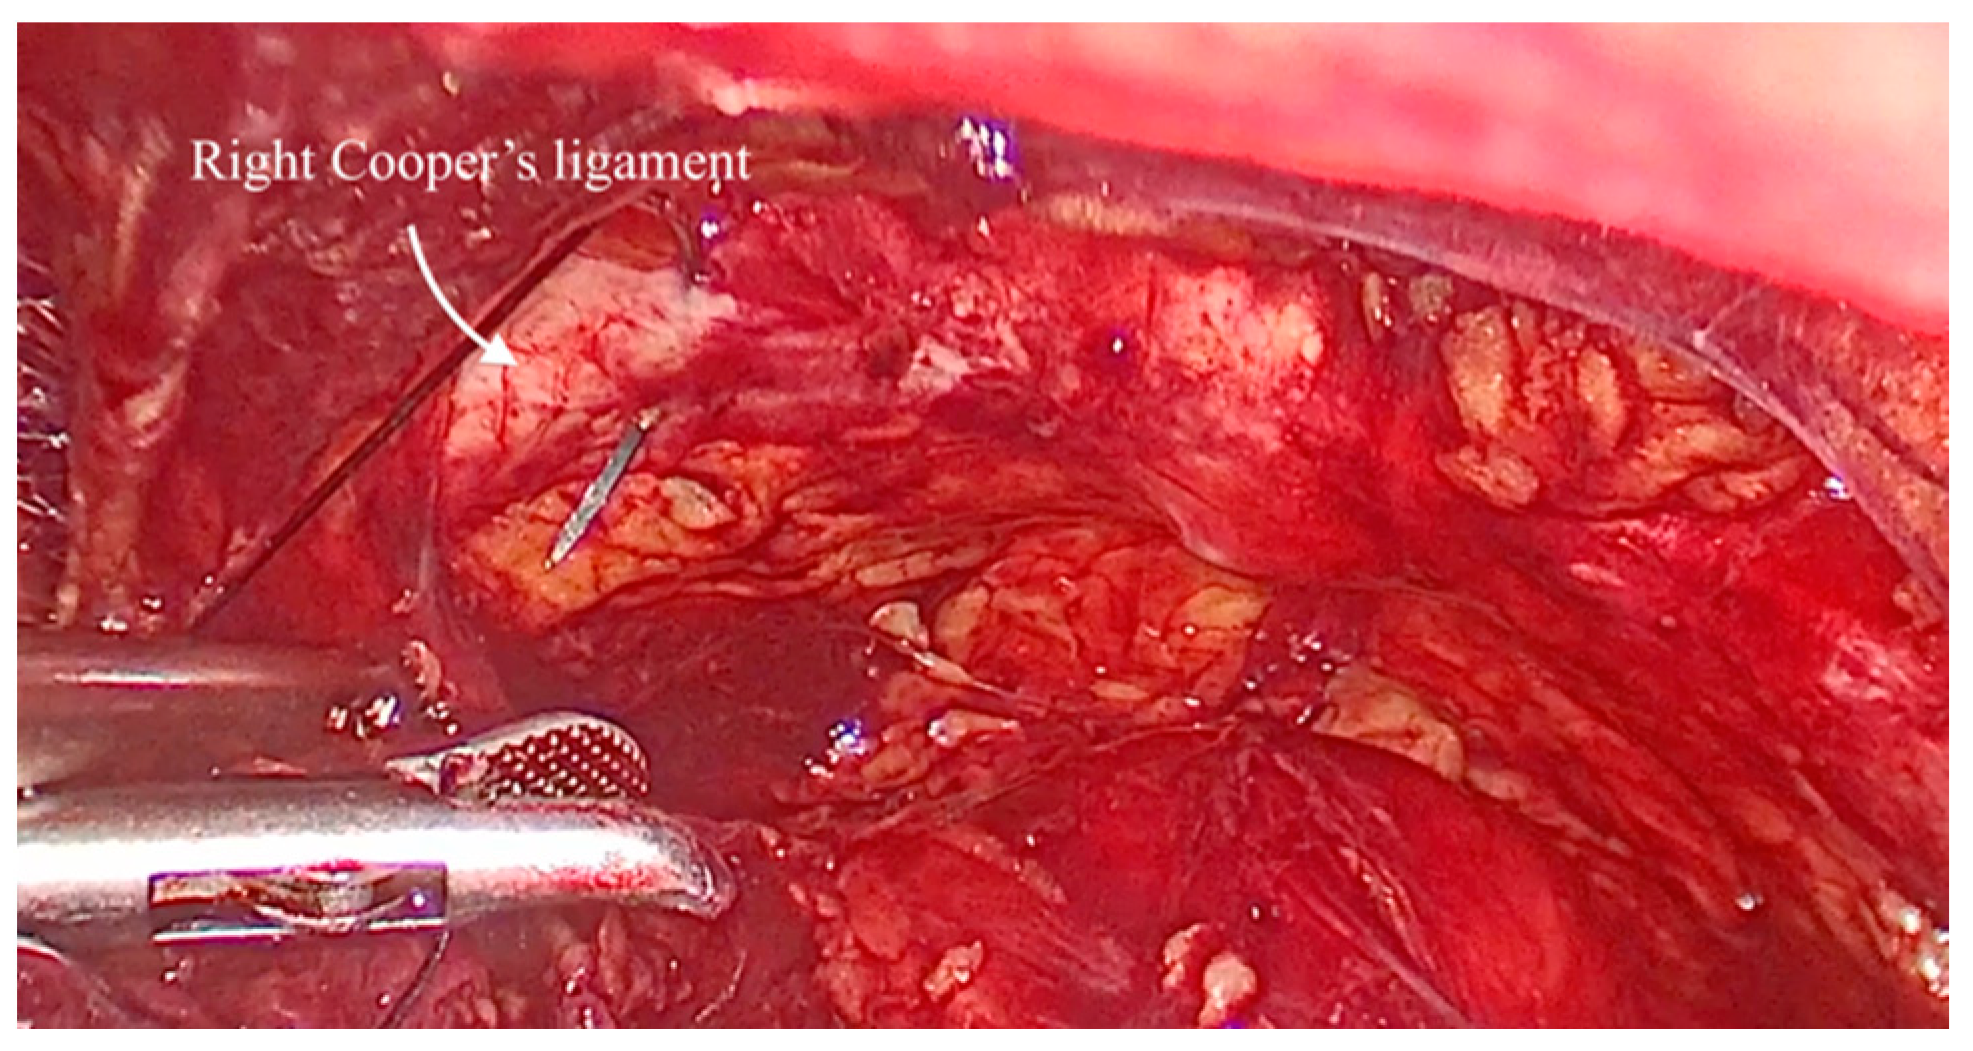

The vaginal walls are identified through blunt dissection. An assistant elevated the vaginal wall via the vaginal route. One suture was placed on each side: a single stitch through the medial portion of each Cooper’s ligament (Figure 2) and two stitches on the vaginal wall below the Foley catheter, positioned in the mid-urethral area (Figure 3). The sutures were tied with intracorporeal knots without applying excessive tension (Figure 4). The parietal peritoneum was then closed using a continuous suture. No drainage was required, and the Foley catheter was removed 24 h postoperatively.

Figure 2. The aspect view of the space of Retzius: iliopectineal line (also known as Cooper’s ligament).